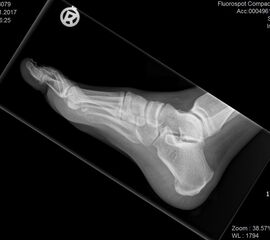

Abbildung 1: Plantarer und dorsaler Sporn im Röntgenbild und im MRT

Abb. 1a und Abb. 1b: großer dorsaler Fersensporn und ein minimaler plantarer Sporn, Patient, 50 Jahre.

Dorsaler Fersensporn: Dorsale Fersenschmerzen können auch durch einen echten dorsalen Fersensporn entstehen (siehe Abb. 1). Dieser entsteht als knöcherne Ausziehung durch Verkalkung der Achillessehne an ihrem Ansatz.